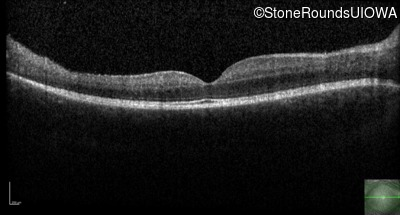

Optical Coherence Tomography - Left - 20/32

Exemplar / OCT Stack